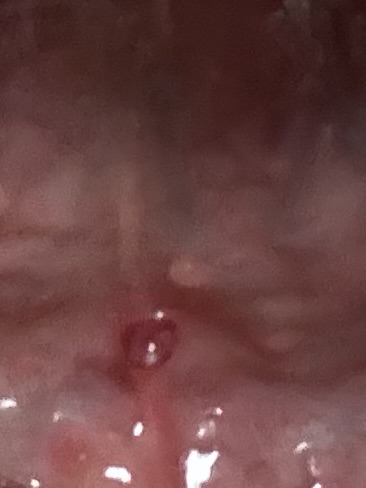

혀 밑쪽에 이상한 돌기가 생겼어요

생긴지는 좀 됐고 작았다가 커졌다가 작았다가 다시 좀 많이 커졌어요 계속 혀로 만지니까 더 커진것같아요

그리고 끝쪽에 여드름처럼 하얀게 있어요

혀 밑의 크기가 변하는 돌기 증상은

침샘 관련 물혹(점액낭종/하마종)일 가능성이 있고

비타민으로 치료할 수 없으므로,

정확한 진단과 치료를 위해 이비인후과나 구강악안면외과를 방문해야 합니다.